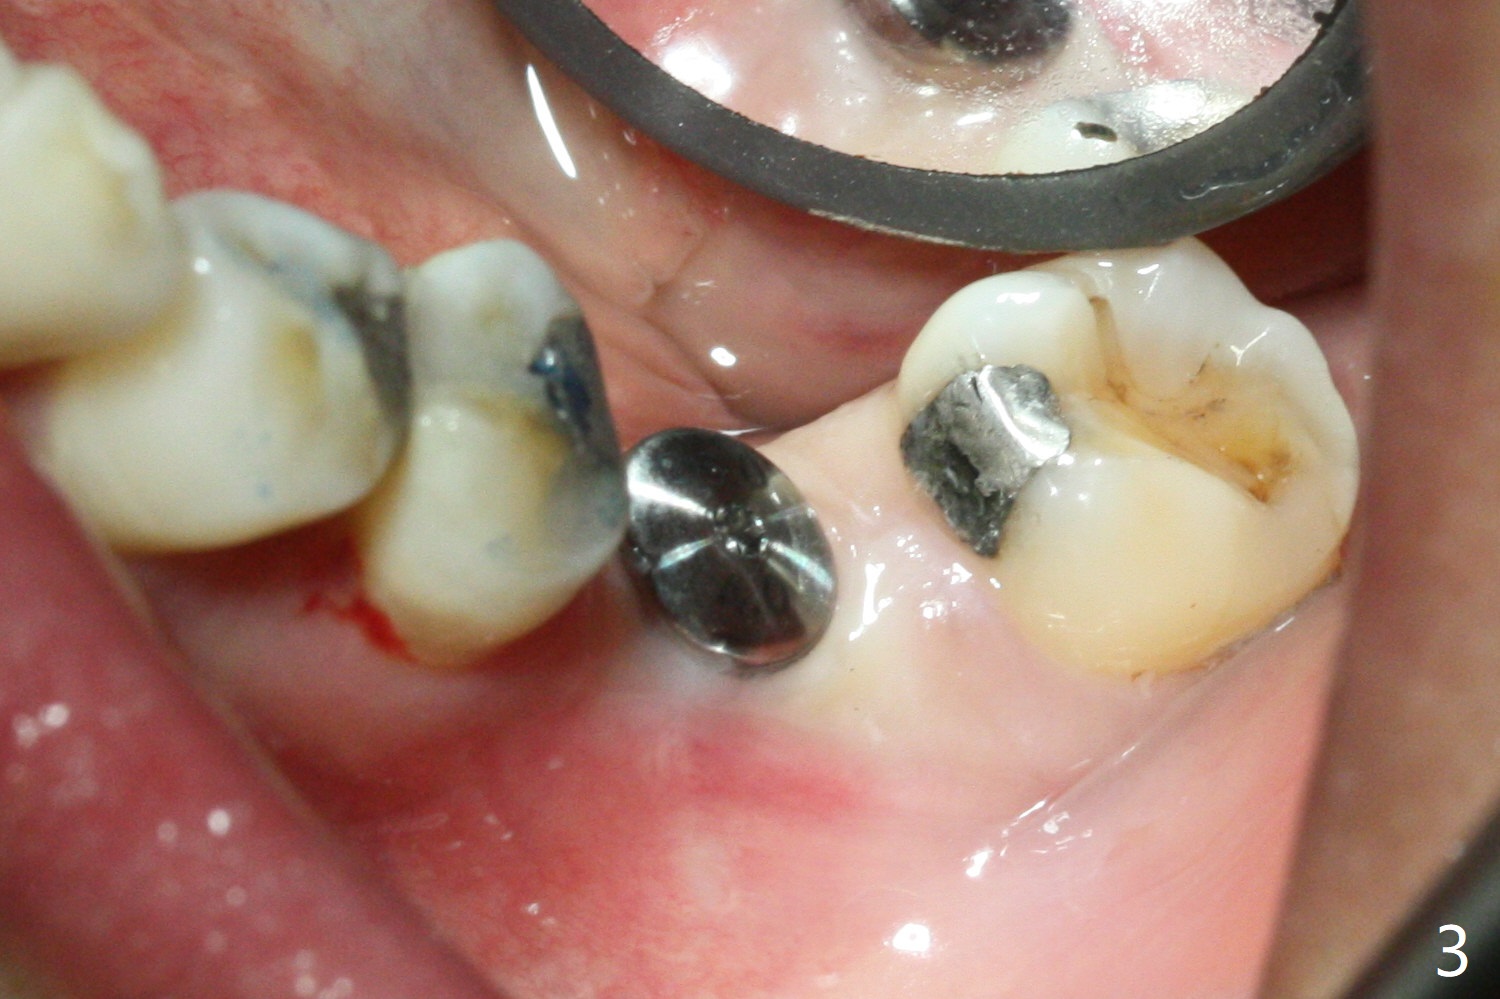

The ridge at #19 is slightly atrophic 5 months post socket preservation (Fig.1). The bone is long enough to hold a 11.5 mm long implant. There is no difficulty in inserting the corresponding drill (4.5x11.5 mm) into the metal sleeve, but the lower right posterior teeth prevent the implant handpiece from going downward completely when the handpiece accesses lingually. Because of the extra manipulation, a 5x10 mm implant achieves insertion torque of ~ 20 Ncm (Fig.2). The implant seems to be seated in the middle of the ridge (Fig.3). The bone density mesial to the implant increases 5 months postop (Fig.4), whereas that distal to the implant remains low 9 months postop (Fig.5). Bitewings taken 2.5 months post cementation (1 year postop, Fig.6,7) show subcrestal placement of the implant (advantage of guided surgery). The implant appears to be well protected; the crestal bone seems to cover the implant plateau. There will be little chance of thread exposure over years of use. The trabecular pattern around the implant is similar to that around the roots of the tooth #30 one year 7 months post cementation (2 years 4 months postop, Fig.8).